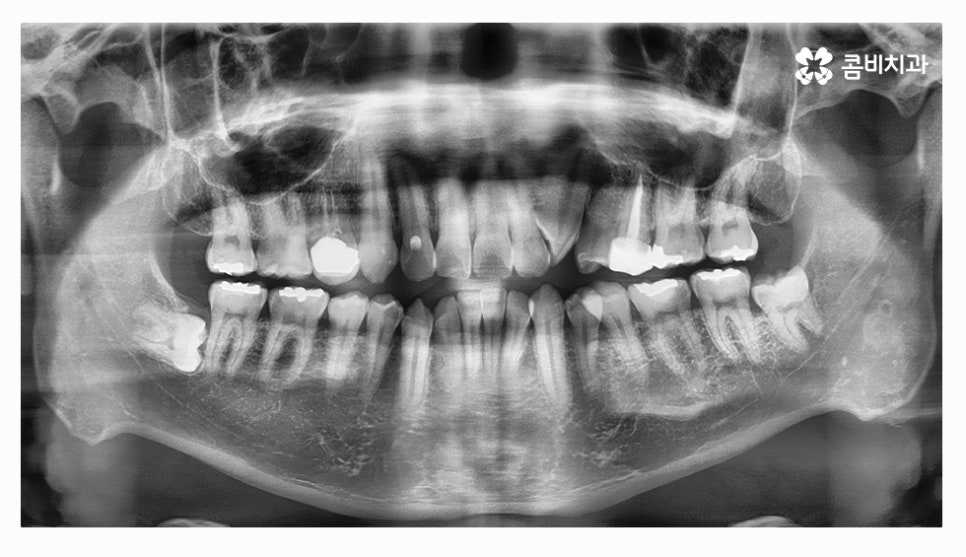

오늘 소개드릴 환자분은 윗니와 아랫니가 제대로 맞물리지 않는

부정교합 사례이며 클리피씨교정을 통해서 치료가 진행된 사례라고 할 수 있어요.

부정교합 환자분들의 경우 발치나 수술이 필요한 경우가 있는데

치아교정을 진행할 때 치아의 이동 공간을 고려해야 하므로

치간 삭제나 어금니 후방 이동으로도 치아 이동 공간이 부족하다면

발치를 필수적으로 해야 하는 경우가 있어요.